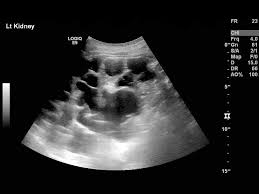

Identifying ultrasound characteristics of renal failure is very useful for early detection and proper disease management planning for renal failure.

Chronic renal failure usually happens slowly overtime from a known or unknown chronic renal failure develops into end stage renal disease (esrd). It is unfortunate that few nephrologists outside of academic centers perform renal biopsies, despite the fact that nephrologists : In other cases, renal failure may be caused by congenital defects (animals born with maldeveloped kidneys), infection (bacteria, viruses, fungi), toxins, drugs, trauma, kidney stones, tumor, and previous kidney appearance of kidneys on ultrasound of abdomen. Gouva c., nikolopoulos p., ionnidis j., siamopoulos k. Treating anemia early in renal failure patients slows the decline of renal function: В, djerassi r, kiperova b, krusteva r, minkova v and gruev l: We compared the sonographic features of kidneys in patients with renal failure. Ultrasound image of renal amyloidosis rosenfield at and siegel n. Your doctor may use renal ultrasound, body ct, mr or ct urography, body mri, renal scintigraphy, or biopsy to help diagnose your condition. Harden pn, macleod mj, rodger rsc, et al. (chronic renal failure can result from a gn). Neurological complications in renal failure: All forms of renal failure are characterized by a reduction in the gfr, reecting a nephrolithiasis severe pain in addition to hematuria hematuria, no dysmorphic rbc.

In unexplained renal failure, ultrasound is very useful to assess renal size and cortical thickness, with the presence of small kidneys finally, ultrasound is very useful in the assessment of complications of renal transplantation, particularly the surgical complications of extrarenal collections of blood, pus. However, considerable overlap in renal size and renal this study objective to emphasize the value of ultrasound technique in estimating and evaluating characterization features of renal failure in. Ultrasound role in renal failure in children 459. How is chronic renal failure treated? Ultrasound imaging findings of femoral veins in patients with renal failure and its impact on vascular access.

Chronic renal failure is how most kidney function decreases. A randomized ayus j., go a., valderrabano f., verde e. Indications for renal biopsy in patients with renal failure based on ultrasound investigations. Ultrasound role in renal failure in children 459. Ultrasound imaging findings of femoral veins in patients with renal failure and its impact on vascular access. Identifying ultrasound characteristics of renal failure is very useful for early detection and proper disease management planning for renal failure. Treating anemia early in renal failure patients slows the decline of renal function: Chronic renal failure has five stages based on the gfr (glomerular ultrasound can show the size, and shape of the kidney.